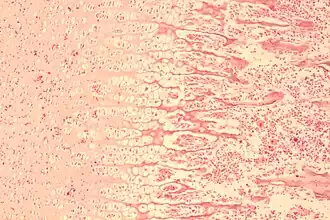

Terwijl osteoblasten osteoïd blijven afscheiden, omringt het bloedvaten, wat leidt tot de vorming van trabekelair (spongieus of sponsachtig) bot. Deze bloedvaten zullen uiteindelijk uitgroeien tot beenmerg. Mesenchymale cellen op het botoppervlak vormen een membraan dat bekendstaat als het beenvlies. Osteoblasten scheiden osteoïd parallel aan de bestaande matrix af, waardoor lagen compact (corticaal) bot ontstaan.[1]

In lange botten verschijnt botweefsel eerst in de diafyse (midden van de schacht). Chondrocyten vermenigvuldigen zich en vormen trebeculae. Kraakbeen wordt geleidelijk geërodeerd en vervangen door verhard bot, dat zich uitstrekt tot aan de epifyse. Een perichondriumlaag rond het kraakbeen vormt het beenvlies, dat osteogene cellen genereert die vervolgens een kraag vormen die de buitenkant van het bot omsluit en de medullaire holte aan de binnenkant hermodelleert. De botkraag ondersteunt het groeiende bot en helpt het zijn vorm te behouden.